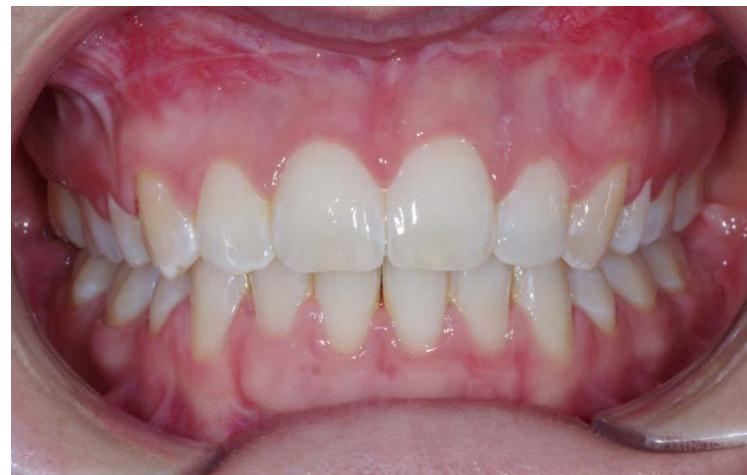

Photos endobuccales de fin de traitement.